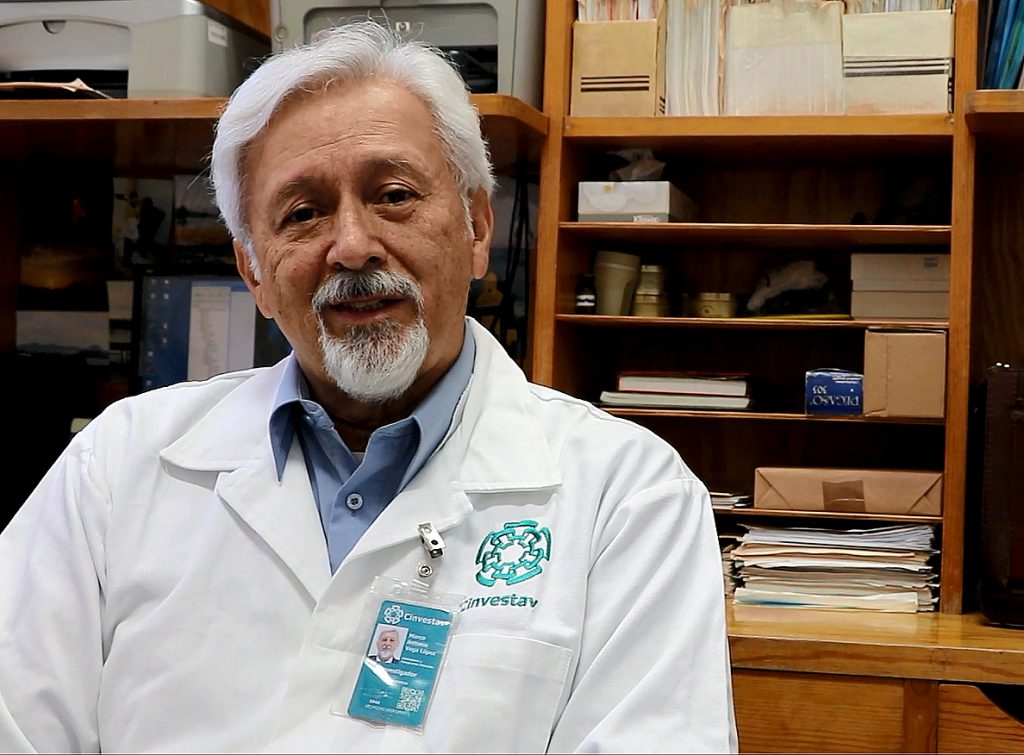

La susceptibilidad a enfermedades infecciosas en la primera etapa de la vida resulta de la presencia temporal de un tipo de células que suprimen la inflamación y con ello regulan la respuesta inmunológica, mencionó Marco Antonio Vega López, profesor adscrito al Departamento de Infectómica y Patogénesis Molecular del Cinvestav.

El investigador participó en un estudio publicado en Frontiers in Immunology, el cual se enfocó en las células eritroides conocidas como CD71+, que son producidas en la médula ósea y frecuentes en los neonatos.

De acuerdo con Vega López, la relevancia de este trabajo radica en que la información obtenida permitirá evaluar cuál es la mejor etapa de vacunación, porque si las células CD71+ suprimen la respuesta inmune y se vacuna tempranamente el resultado podría no ser el óptimo.

Este tipo de estudios permite entender mejor la relación materno-infante a nivel inmunológico, así como destacar la relevancia del parto natural y la lactancia materna para dotar al recién nacido de anticuerpos y facilitar que la microbiota se instale de manera adecuada, dijo Vega López.

Por lo cual, agregó el especialista del Cinvestav, sería necesario continuar con los estudios acerca de las células CD71+ en diferentes contextos, como en la preeclampsia (principal causa de muerte materna y neonatal) o la vacunación perinatal. (EL HERALDO)